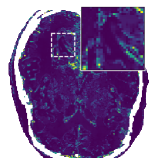

In Figure 12 we compare the PD3O reconstructions (top) and their corresponding errors with respect to the ground truth (bottom) using different regularization parameter choices , and for PD3O. Obviously, using the estimated parameter-map leads to a significant improvement of the reconstruction. In particular, sharp edges are retained, while using a constant regularizing parameter results in a significant blur. This can be also seen in Table 4, where we compare the NRMSE, PSNR, SSIM and blur and evaluated on the first 100 test images of the LoDoBaP dataset. These results are visualized in Figure 13 using box-plots. Note that the FBP seems to better than PD3O- in terms of the blur effect, but this can be explained by the fact that FBP reconstructions admit a lot of high-frequency artefacts leading to a small blur effect.

Further PD3O- reconstructions with their corresponding estimated parameter-maps are shown in Figure 14. Note that the parameter-maps are given in a logarithmic scale. As expected, the regularization is strong in constant areas and less strong on edges or finer details in order to reduce a smoothing in these regions.